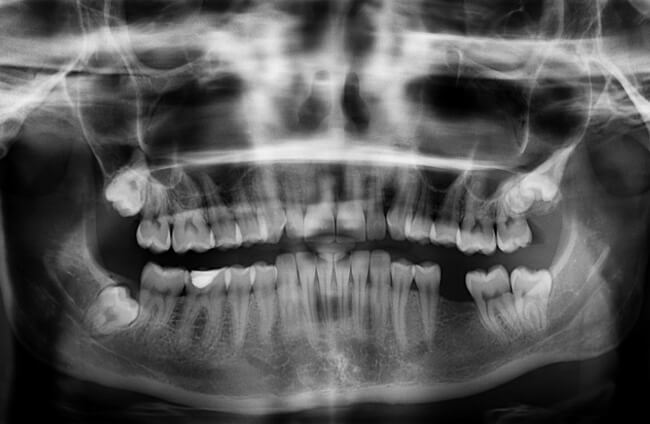

Dental X-rays are important because they allow your dentist to see your teeth, gums, and jaw in great detail—a much higher degree than they could see with the naked eye. Your mouth could be changing in ways you’re not aware of, and it’s important for your dentist to see and note these changes in order to catch problems while they’re still small and take the necessary next steps to protect your health as soon as possible.